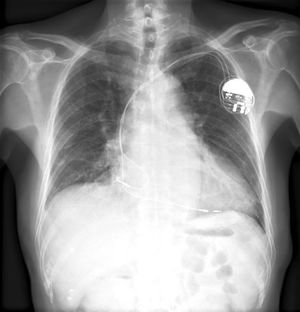

Plain Film Findings

- Obtain PA/Lateral Films to confirm pulse generator, manufacturer, lead placement/number/integrity

- R atrial lead J shaped(tip medially on AP) entering right atrial appendage

- RV leads point downward with tip between left spine and cardiac apex--lateral XR shows inferior and anterior

- Coronary sinus lead- courses posteriorly on lateral XR

- Extra leads may be appropriately abandoned and capped

- ICD component appears as thickened shock coil